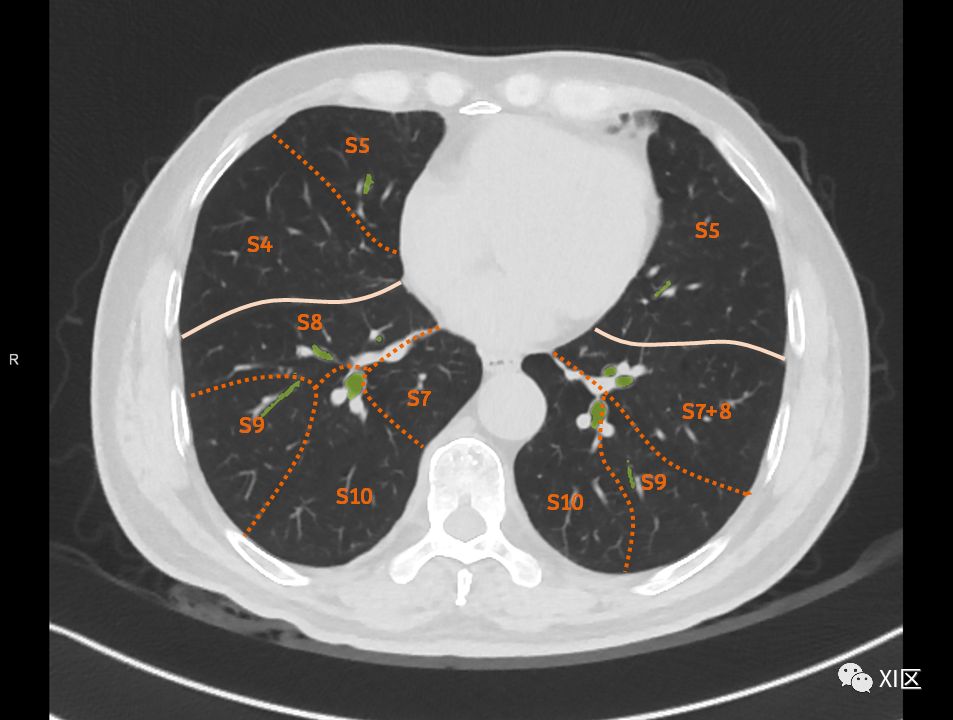

肺的断层分段示意图

在进行肺的分段时,可以上下观察浏览,沿着相应气管的走形可以更容易准确地进行分段。